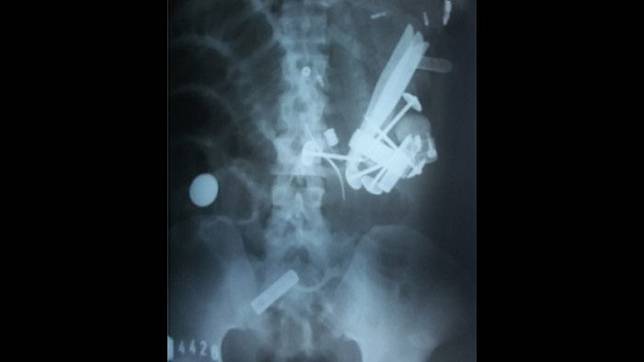

Hasil rontgen yang menunjukkan banyak logam di perut Hendro Wijatmiko.

muncul. Adanya paku payung dan benda tajam lain dalam usus tersebut diketahui setelah hasil rontgen polos RS yang merujuknya,